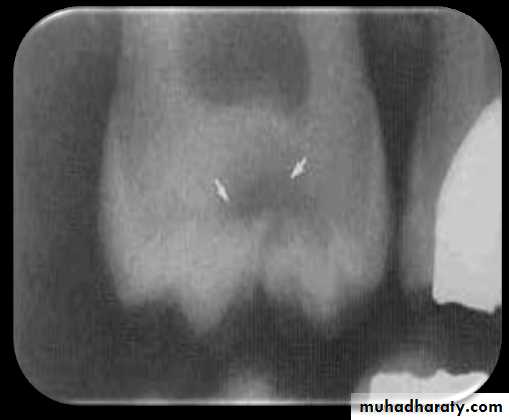

Buccal and Lingual Caries

Buccal caries involve the buccal tooth surface.

Lingual caries involve the lingual tooth surface.

Because of superimposition of the densities of normal tooth structure, they are difficult to be detected by the dental radiograph and are best detected clinically.

Radiographically these carious lesions appear as a small circular radiolucent area.